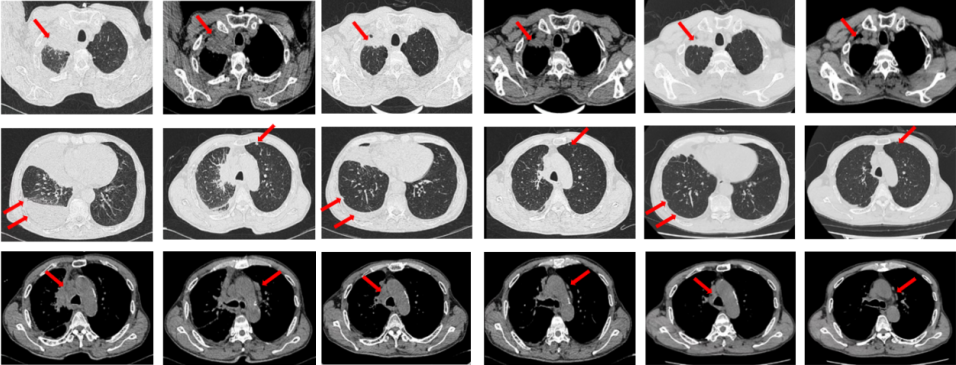

2024年10月复查出现PD,后因患者病情迅速恶化进入肿瘤姑息治疗。该患者的全部诊治经过如图4所示。

图4:该患者的诊治经过。

如图7所示,2021年7月复查评效PD。重新行右肺穿刺取得病理,提示腺癌。NGS组织基因检测:MET基因扩增(变异倍数)4.0倍。改行赛沃替尼联合奥希替尼治疗。治疗10日后突发一过性寒战伴低血压,不除外药物相关,对症治疗后好转。复查评效达PR,因患者无法耐受药物不良反应,改行奥希替尼联合克唑替尼治疗至今,定期复查,最佳评效PR,末次评效SD(2024年7月)。

图8:第2例患者的整体诊治过程